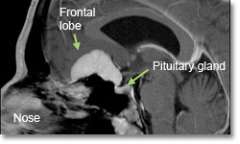

MRI of a meningioma tumor

MRI image showing a typical meningioma tumor

• Magnetic resonance imaging (MRI) scans effectively detect most meningiomas and are best at displaying details of the brain.